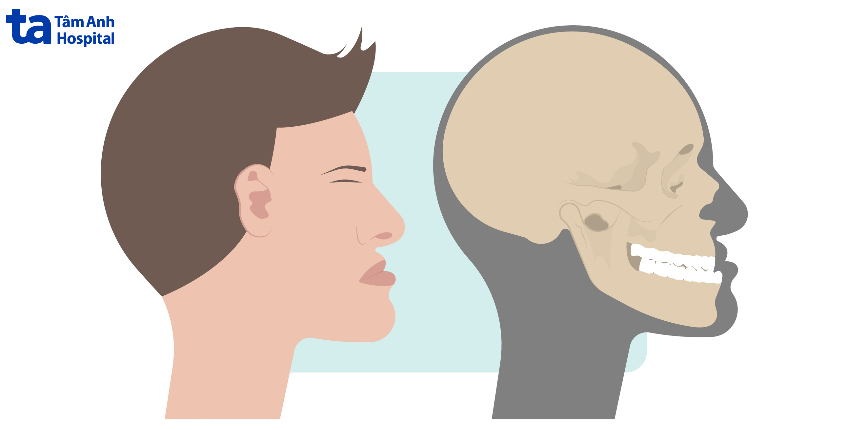

Sai khớp cắn loại 3 là tình trạng hàm răng dưới trượt ra phía trước nhiều so với hàm trên, dẫn đến 2 hàm không có sự tương quan, múi ngoài gần của răng hàm lớn vĩnh viễn thứ nhất ở hàm trên khớp về phía xa so với rãnh ngoài gần của răng hàm lớn vĩnh viễn thứ nhất ở hàm dưới.

Sai khớp cắn loại 3 thường thường phân thường 2 loại: do răng hoặc do xương.

Đây là tình trạng răng vẫn mọc đúng vị trí nhưng xương hàm dưới phát triển quá mức, hàm trên ngắn và sụp vào trong. Ngoài ra, răng móm do biến dạng hở hàm ếch có thể dẫn đến thiếu kích thước theo chiều ngang ở hàm trên. Từ đó làm các răng cửa hàm trên luôn nằm ở vị trí trung gian so với các răng cửa hàm dưới. Sai khớp cắn do xương vẫn có thể khắc phục hoàn toàn bằng phẫu thuật nếu được can thiệp từ sớm.